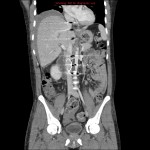

- Reformatted abdominal CT: There is an OptEase filter in the inferior vena cava